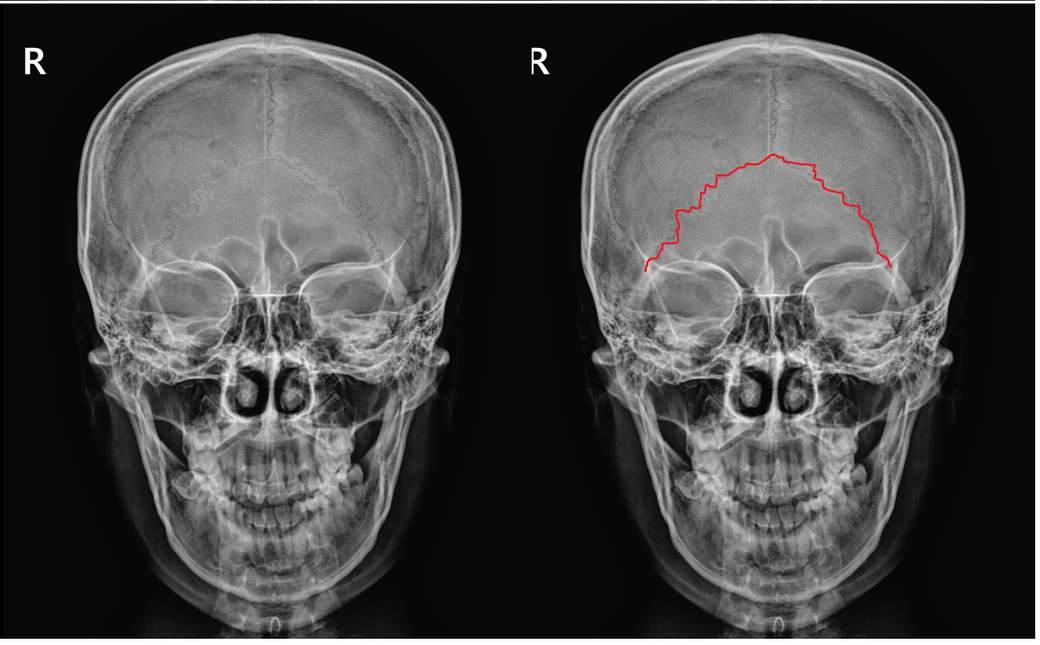

사진속 표시한 부분 전두골이 아니라 후두골 인가요?

빨간색으로 표시한 부분이 두정골과 후두골이 만나는 부분이죠? 전두골이 아니라.

이게 앞모습이라 전두골인줄 알았는데 뒤통수 부분이 투과되서 나오는거죠?

전두골 봉합은 왜 안보이는거죠?

아래 그림의 오른쪽 그림 보시면 두정골과 후두골이 만나는 부위를 보실 수 있을겁니다. 이게 전면부에서 보면 작성자분이 올려주신 X-ray와 같이 삼각형 모양으로 보일 수 있습니다. 작성자분이 표현하셨듯이 투과되어서 앞에서 삼각형으로 보이는겁니다.

전두골이 그 아래 뼈들과 만나는 부위는 아래 그림에 보시듯이 안구가 들어가는 안와부위입니다. 그런데 X-ray상에 두개골의 기저부와 비슷한 높이에 있어서 구분하기가 어려운 경우가 많습니다.

아마 이마에 봉합섬이 있지 않을까 생각하셨을텐데 아래 그림 보면 그게 아니라 안와에 있다는걸 이해하기 쉬우실겁니다.

사진에서 빨간색으로 표시된 부분은 전두골이 맞아요 전두골은 이마 부분을 포함하는 뼈로 두정골과 봉합되는 부분이 있습니다 후두골은 뒤통수에 위치하고 이 부분이 아니라 앞부분의 전두골이기 때문에 봉합선이 보이지 않는 것입니다!